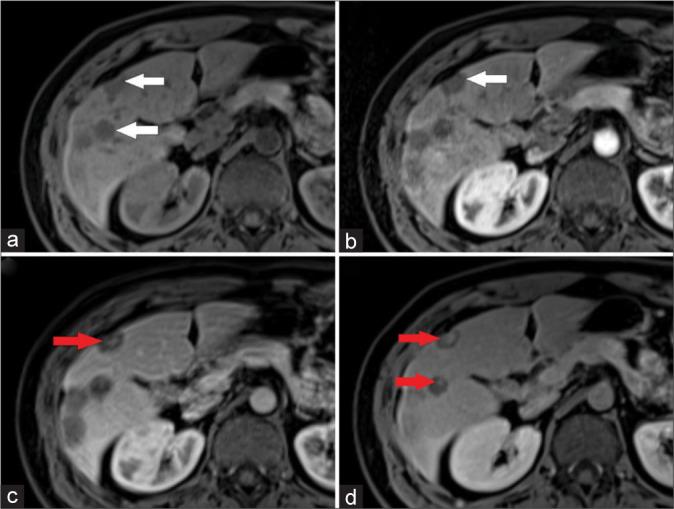

25岁男性多发原发性肝血管肉瘤的MRI及PET/CT表现:病例报告

This study aims to provide a comprehensive understanding of primary hepatic angiosarcoma, a rare and aggressive malignancy, focusing on its diagnostic challenges and unique imaging characteristics. The objective is to delineate the distinctive features of angiosarcoma through computed tomography and magnetic resonance imaging modalities, contributing to improved diagnostic precision and adding valuable insights to the scientific literature. We present the case of a 25-year-old male with primary hepatic angiosarcoma, emphasizing the challenges in distinguishing it from other vascular tumors.

本研究旨在全面了解原发性肝血管肉瘤,这是一种罕见且侵袭性强的恶性肿瘤,重点关注其诊断挑战和独特的影像学特征。目的是通过计算机断层扫描和磁共振成像方式描绘血管肉瘤的独特特征,有助于提高诊断准确性,并为科学文献增添有价值的见解。我们报告了一例25岁男性原发性肝血管肉瘤病例,强调了将其与其他血管肿瘤区分开来所面临的挑战。